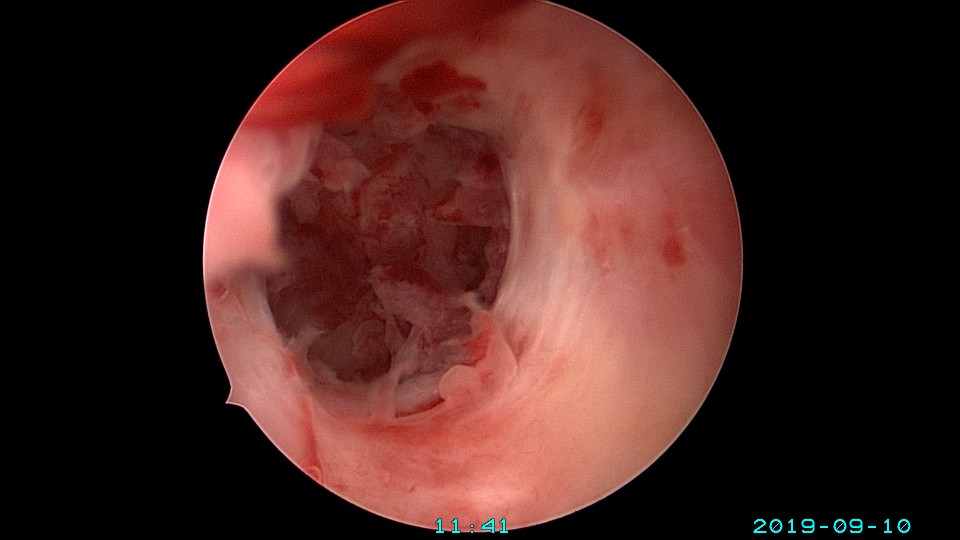

患者26岁,G1P0 ,2019年9月门诊宫腔镜检查发现宫腔重度粘连,2019年10月住院宫腔镜分粘,恢复宫腔形态,显露双侧输卵管开口。2019年11月宫腔镜二探取球囊,宫腔形态正常,双侧输卵管开口可见。2021年3月发现自然妊娠,后因先兆流产、胎心弱在当地医院险些清宫终止妊娠,病人电话咨询我,嘱病人千万不要急着清宫,立即到我院复查,心管搏动良好,住院保胎成功,2021年11月,39周孕剖宫产分娩。2023年7月,再次自然妊娠,39+3周孕剖宫产分娩。现31岁,G3P2。